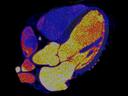

More and more radiologists are relying on the rich diagnostic possibilities offered by True Dual Energy imaging on Siemens Healthineers' CT scanner fleet ranging from SOMATOM® Scope Power up to the outstanding SOMATOM Force.

The question is: What makes True Dual Energy stand out? Look for these three criteria: crisp images with the option for even sharper contrast and significant artifact reduction; no extra dose in either Single Source or Dual Source Dual Energy scans, and a broad applicability for virtually all clinical questions and patients.

Discover Dual Energy (DE) spectral imaging. It’s the difference between images and answers. Visualization and characterization. Qualification and quantification. Built into all of our CT scanners, it delivers powerful performance, incredible versatility for your entire patient population, and exceptional ease-of-use – all while integrating seamlessly with your current workflow.